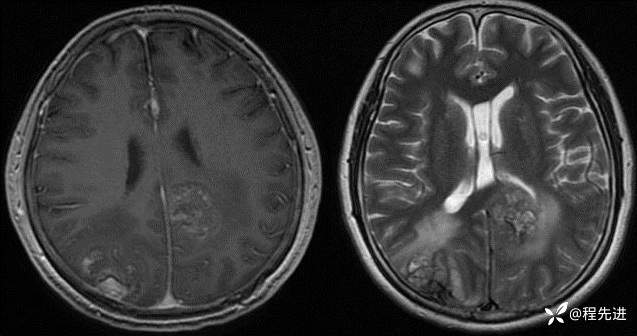

半年后:

img